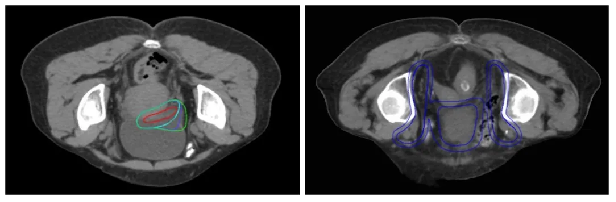

为了既达到理想的剂量效果,又保证膀胱状态的高重复性,放疗科何立儒主任医师为王阿叔制定了“先充盈7分次再排空23分次”的两段式放疗方案。其中充盈膀胱的7个分次仅对肿瘤进行推量并将这个阶段置于前,尽可能避免患者因放疗刺激而出现尿控能力下降的情况,排空膀胱的23个分次则对全膀胱及引流区进行照射。

“先充盈再排空”两段式放疗靶区示意图